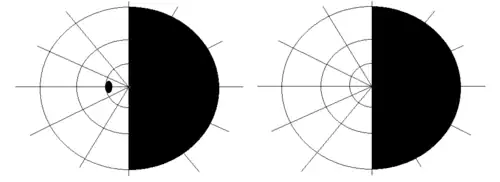

| |

| Visual pathway lesions From top to bottom: 1. Complete loss of vision in the right eye 2. Bitemporal hemianopia 3. Homonymous hemianopia 4. Quadrantanopia 5.& 6. Quadrantanopia with macular sparing | |

The type of field defect can help localize where the lesion is located (see picture given in infobox).